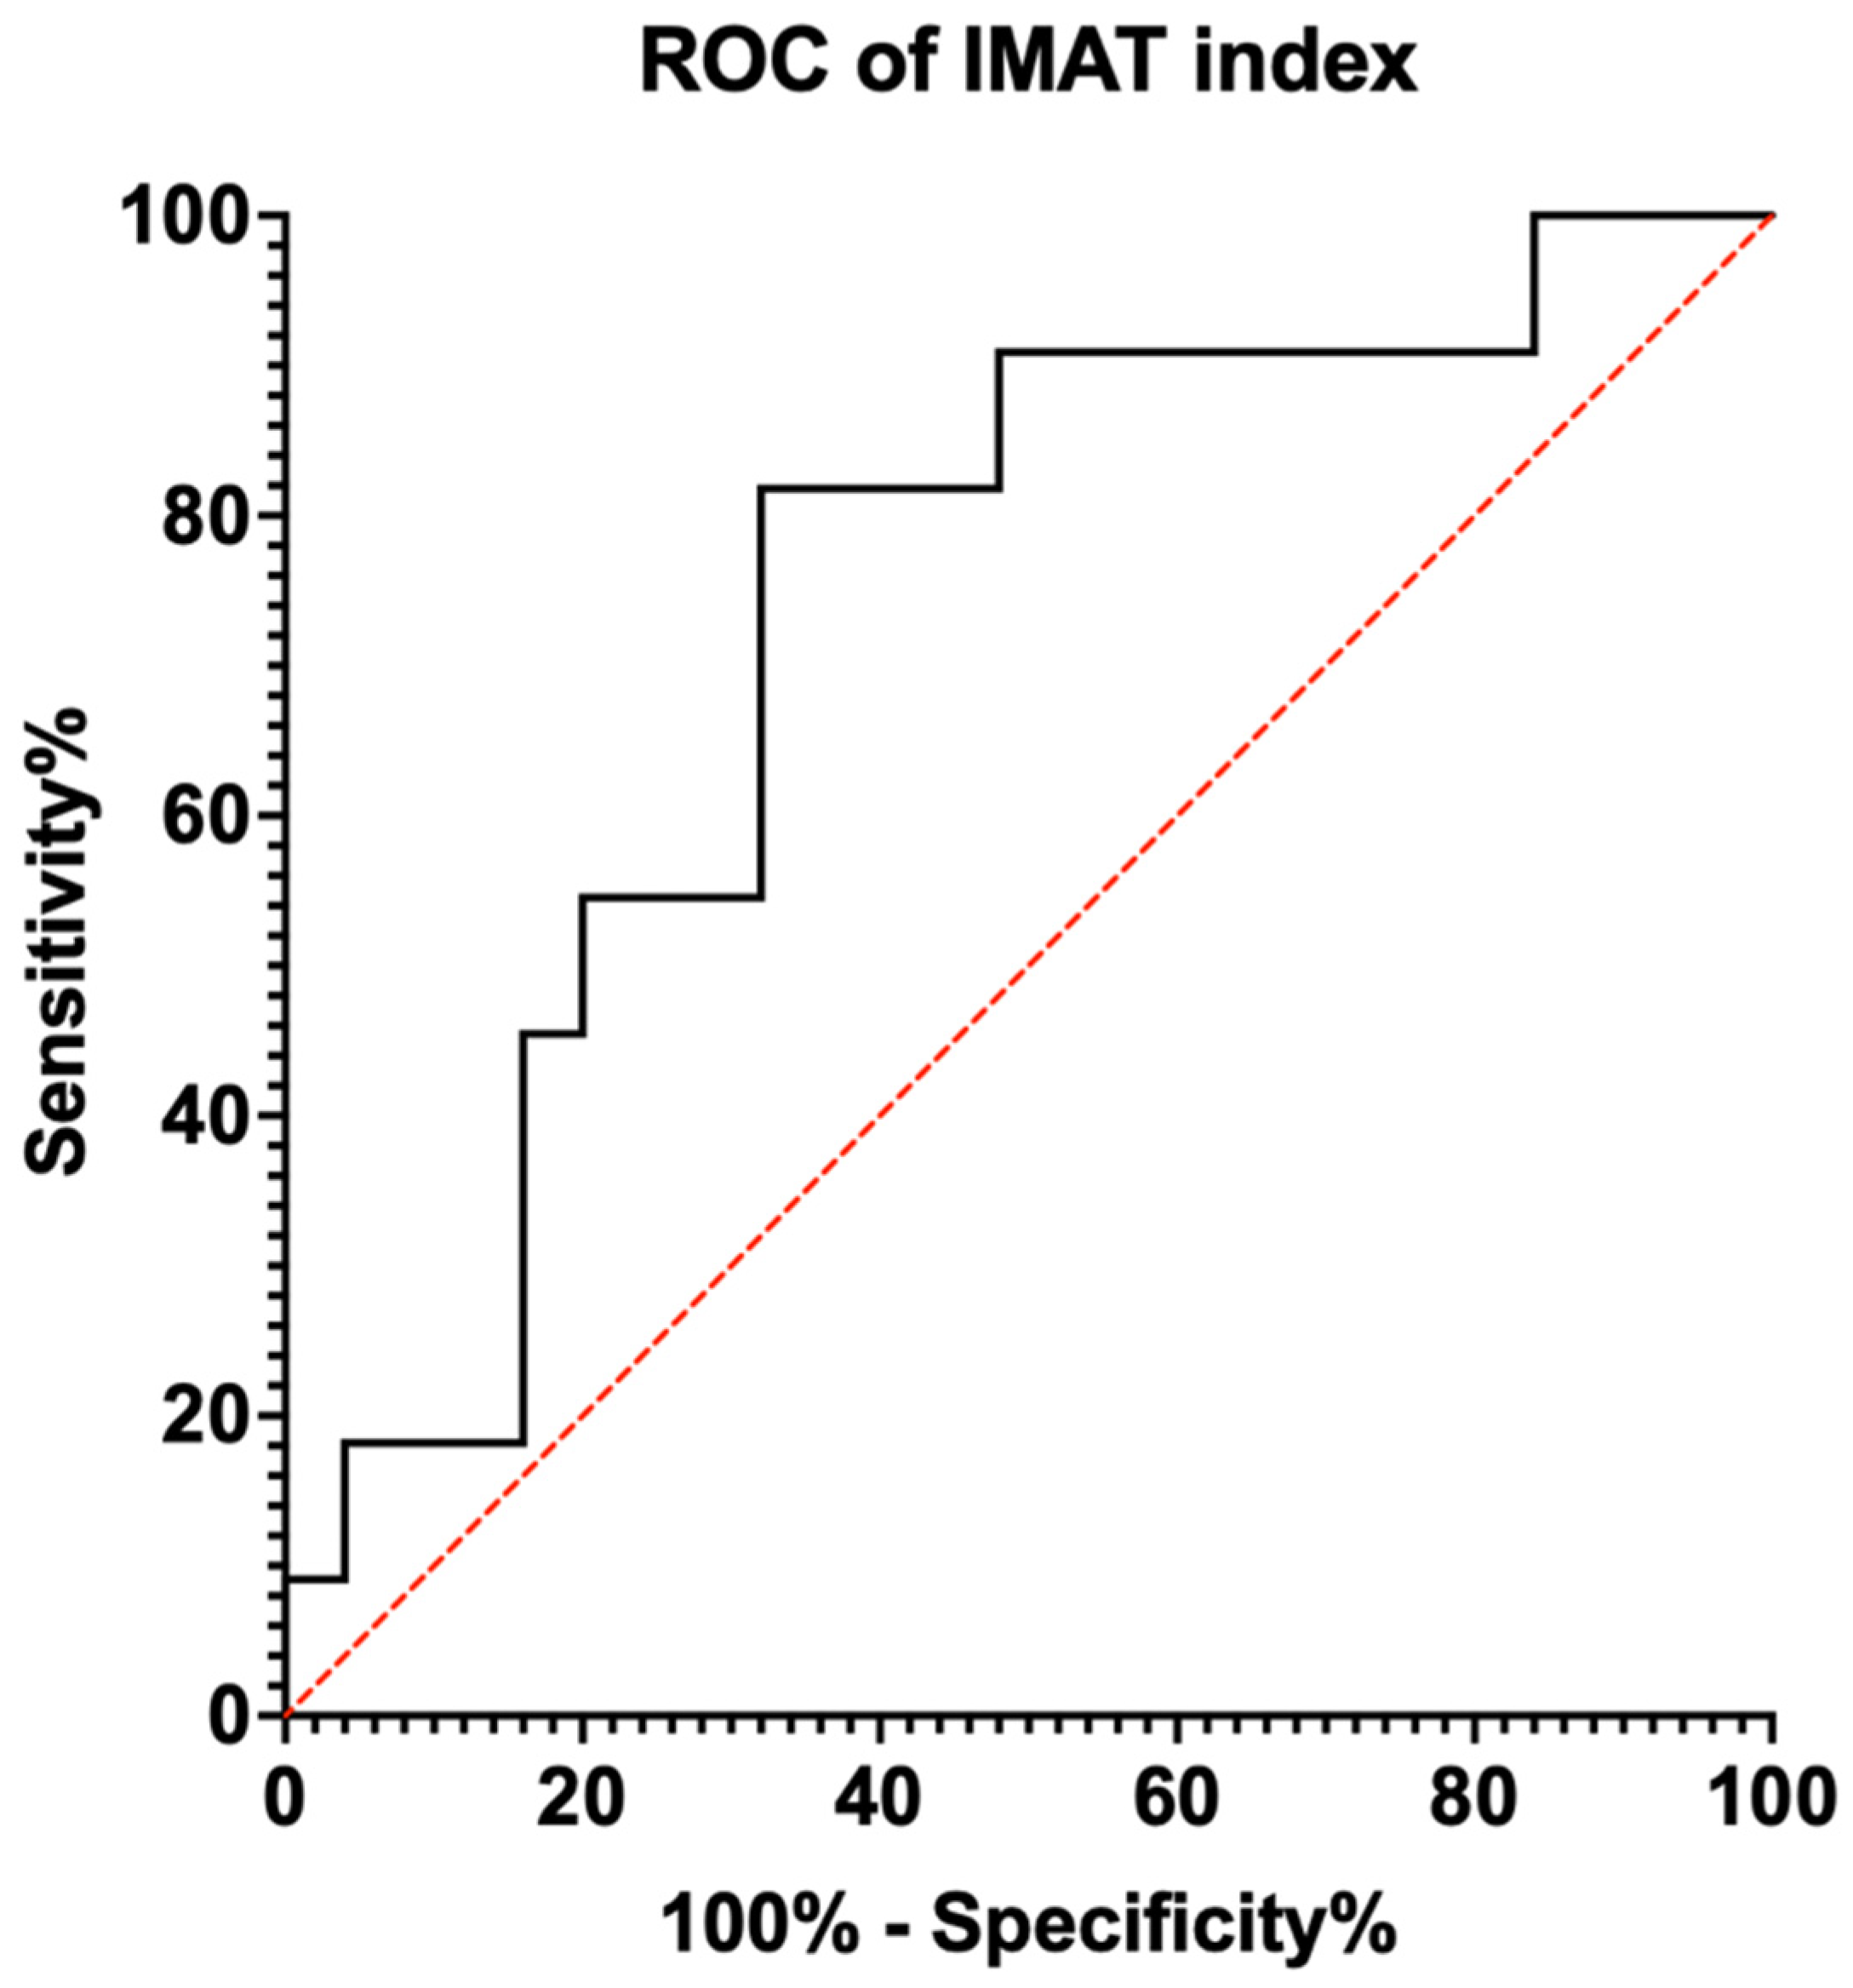

3.2. Diagnostic Capability

| Cut-Off Value | Sensitivity | 1—Specificity | Youden’s Index |

|---|---|---|---|

| 2.7938 | 1.000 | 0.840 | 0.160 |

| 2.9705 | 0.909 | 0.760 | 0.149 |

| 3.3220 | 0.909 | 0.640 | 0.269 |

| 3.6830 | 0.909 | 0.560 | 0.349 |

| 3.7703 | 0.909 | 0.520 | 0.389 |

| 3.9598 | 0.909 | 0.480 | 0.429 |

| 4.6990 | 0.818 | 0.400 | 0.418 |

| 4.7275 | 0.818 | 0.360 | 0.458 |

| 4.8265 | 0.818 | 0.320 | 0.498 |

| 5.0920 | 0.727 | 0.320 | 0.407 |

| 5.3387 | 0.636 | 0.320 | 0.316 |

| 5.5428 | 0.545 | 0.280 | 0.265 |

| 5.7083 | 0.545 | 0.200 | 0.345 |

| 6.0910 | 0.455 | 0.200 | 0.255 |

| 6.9270 | 0.364 | 0.160 | 0.113 |

| 7.3528 | 0.182 | 0.160 | 0.022 |

| 7.8985 | 0.182 | 0.120 | 0.062 |